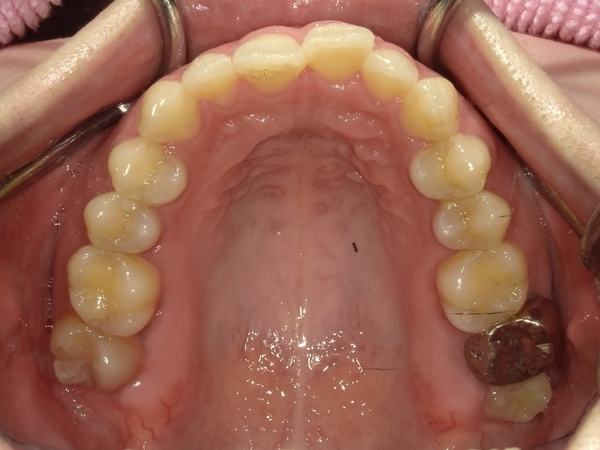

ガタガタとした歯並びや八重歯(叢生)CASE66